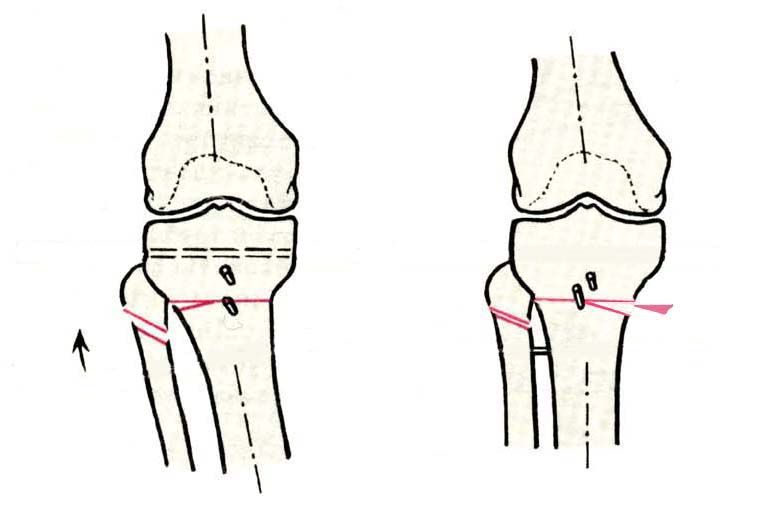

Поводом для проведения всех корригирующих остеотомий у исследуемых пациентов служил гонартроз 1-3 стадии, косметическая коррекция в большинстве случаев являлась вторичной.

Хотя любого больного она не в меньшей степени интересовала. При всех видах остеотомий обязательным требованием являлась восстановление баланса пассивных и динамических сил путем восстановления оси конечности, стабильности связочного аппарата и контроля над мышечной активностью при осевой нагрузке. Как правило, учитывалась сохранность гиалинового хряща на компенсирующем нагрузку мыщелке бедра или большеберцовой кости. Предоперационное планирование осуществляли с поднагрузочных рентгенограмм обоих конечностей.

Дополнительными методами диагностики являлось измерение внутрикостного давления в зоне гипернагрузки и радионуклидные исследования нуклидами технеция. Применялись различные варианты остеотомий на различных сегментах. Для коррекции варусной-торсионной деформации:

высокие плюс, минус остеотомии большеберцовой кости,косая остеотомия малоберцовой. Для коррекции вальгусной деформации применялась плюс, минус надмыщелковая остеотомия бедренной кости. Фиксацию при высокой подмыщелковой остеотомии производили уникальной клинковой пластиной и тяговыми кортикальными винтами. Угол коррекции выставлялся

специальным угломером и направителем.